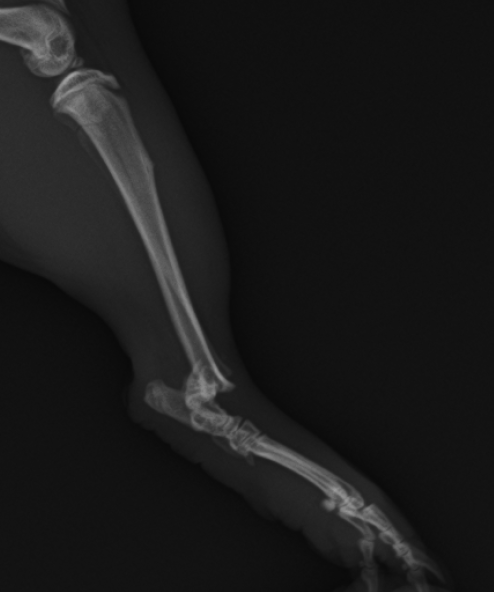

モルモットが後肢をかばっている(後肢:脛骨の骨折) 公開済み: 2024年11月12日更新: 2025年11月2日作成者: koizumi-nest モルモットの骨折は、特に後肢の脛骨(すねの部分)においてよく発生します。 特に若いモルちゃんによく見られるように感じられます。 骨折の仕方によって、手術による整復と固定を実施する必要があります。 モルモットの脛骨の骨折レントゲン写真。 踵関節の近くで骨折しています。整復・固定手術を行いました。 手術し、ギプス固定した後のレントゲン写真。 固定を外した後のレントゲン写真。 良好に骨癒合しており、これで治療は終了となりました。